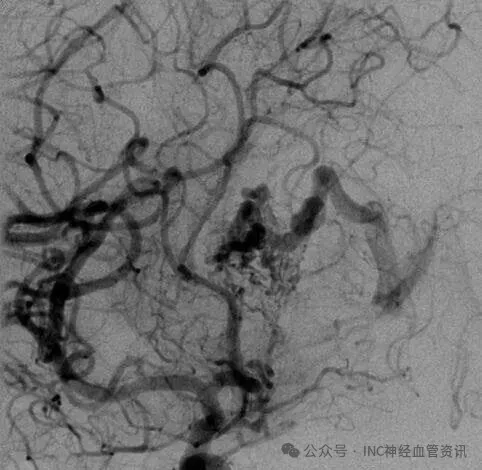

Anna的AVM由多條動(dòng)脈供血:ACA/PcaA分支、ACoA穿支和mPChA,形成了一個(gè)復(fù)雜的血管網(wǎng)絡(luò)。首次伽馬刀治療后,血管團(tuán)部分閉塞,但殘留的畸形血管仍然構(gòu)成出血威脅。

▼該AVM由ACA/PcaA分支、ACoA穿支和mPChA供血[右側(cè)ICA造影